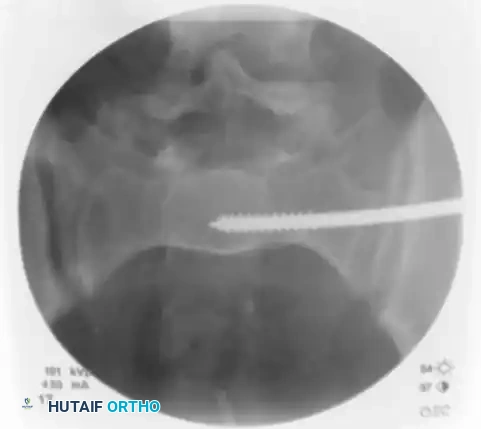

Remove the inner trocar, leaving the cannulated sleeve docked in the bone. Insert a threaded 2.8 mm or 3.2 mm guidewire into the sleeve.

Image

Utilizing biplanar fluoroscopic imagery—rapidly alternating between the inlet and outlet views—adjust the trajectory of the guide sleeve to safely target the center of the S1 vertebral body.

• On the Inlet View: Aim for the center of the sacral body, staying well posterior to the anterior sacral cortex and anterior to the spinal canal.

• On the Outlet View: Aim between the S1 superior endplate and the S1 neuroforamen.

Once the trajectory is perfected, advance the guidewire under power across the sacroiliac joint and into the sacral ala.

Stop advancing just before the midline. Confirm safe passage on both the inlet and outlet views.